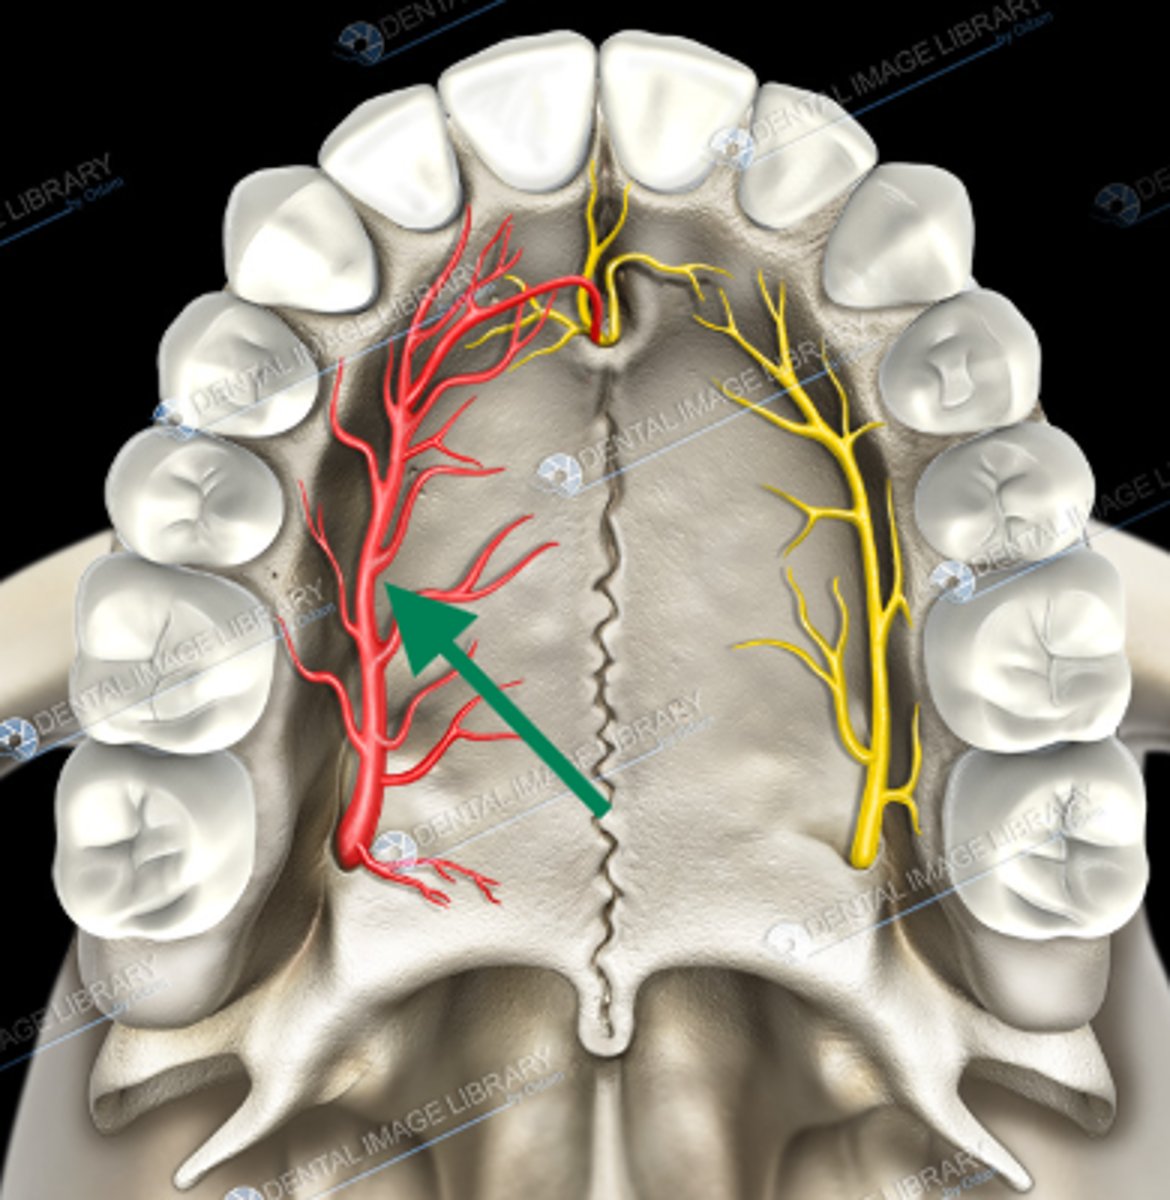

nasopalatine nerve

descending palatine artery

greater palatine nerve

greater palatine artery

greater palatine foramen

lesser palatine nerve

lesser palatine artery

greater and lesser palatine nerve

greater palatine nerve